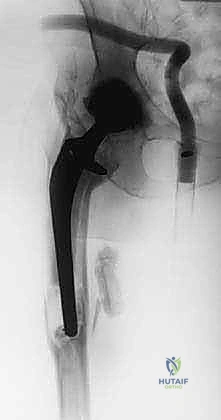

- الأشعة السينية الرقمية (Digital X-rays): لتقييم وضع المفصل الحالي، وتحديد مقدار العظم المفقود، وتصنيف حالة العظم.

الخطوات الجراحية: كيف تتم عملية استبدال الجزء العلوي من الفخذ؟

هذه الجراحة هي بمثابة عمل هندسي دقيق داخل جسم الإنسان. بفضل استخدام تقنيات الجراحة الميكروسكوبية وخبرته الطويلة، ينفذ الأستاذ الدكتور محمد هطيف هذه العملية عبر خطوات مدروسة ومحكمة:

5. تجميع وزراعة المفصل المعياري (Modular Prosthesis Implantation)

هنا تتجلى روعة التكنولوجيا الطبية الحديثة. بدلاً من مفصل بقطعة واحدة، يستخدم الدكتور هطيف "مفصل معياري" يشبه قطع تركيب (Lego). يتكون من:

* الجذع السفلي (Distal Stem): يتم تثبيته في العظم السليم المتبقي في منتصف أو أسفل الفخذ (غالباً بدون أسمنت عبر النمو العظمي، أو باستخدام الأسمنت حسب حالة العظم).

* الجسم (Body/Segment): قطع معدنية أسطوانية بأطوال مختلفة لتعويض العظم المفقود بدقة واستعادة طول الساق الطبيعي.

* العنق والرأس (Neck and Head): يتم اختيار الزاوية والطول المناسبين لضمان استقرار المفصل وتوتر العضلات.

يتم تجميع هذه القطع وتثبيتها ميكانيكياً بقوة هائلة داخل غرفة العمليات لتشكيل عظم فخذ اصطناعي كامل.

![الأشعة السينية بعد العملية](/media/huta